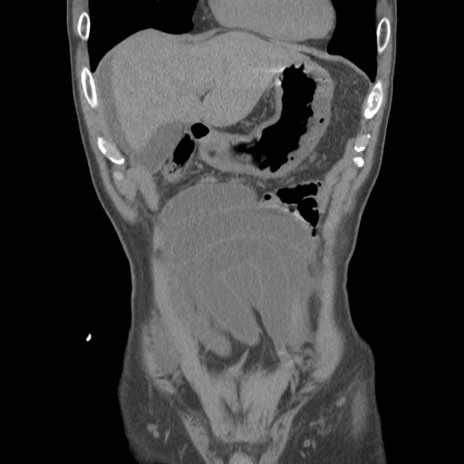

症例56 CT(冠状断像)

脂肪ウインドウ